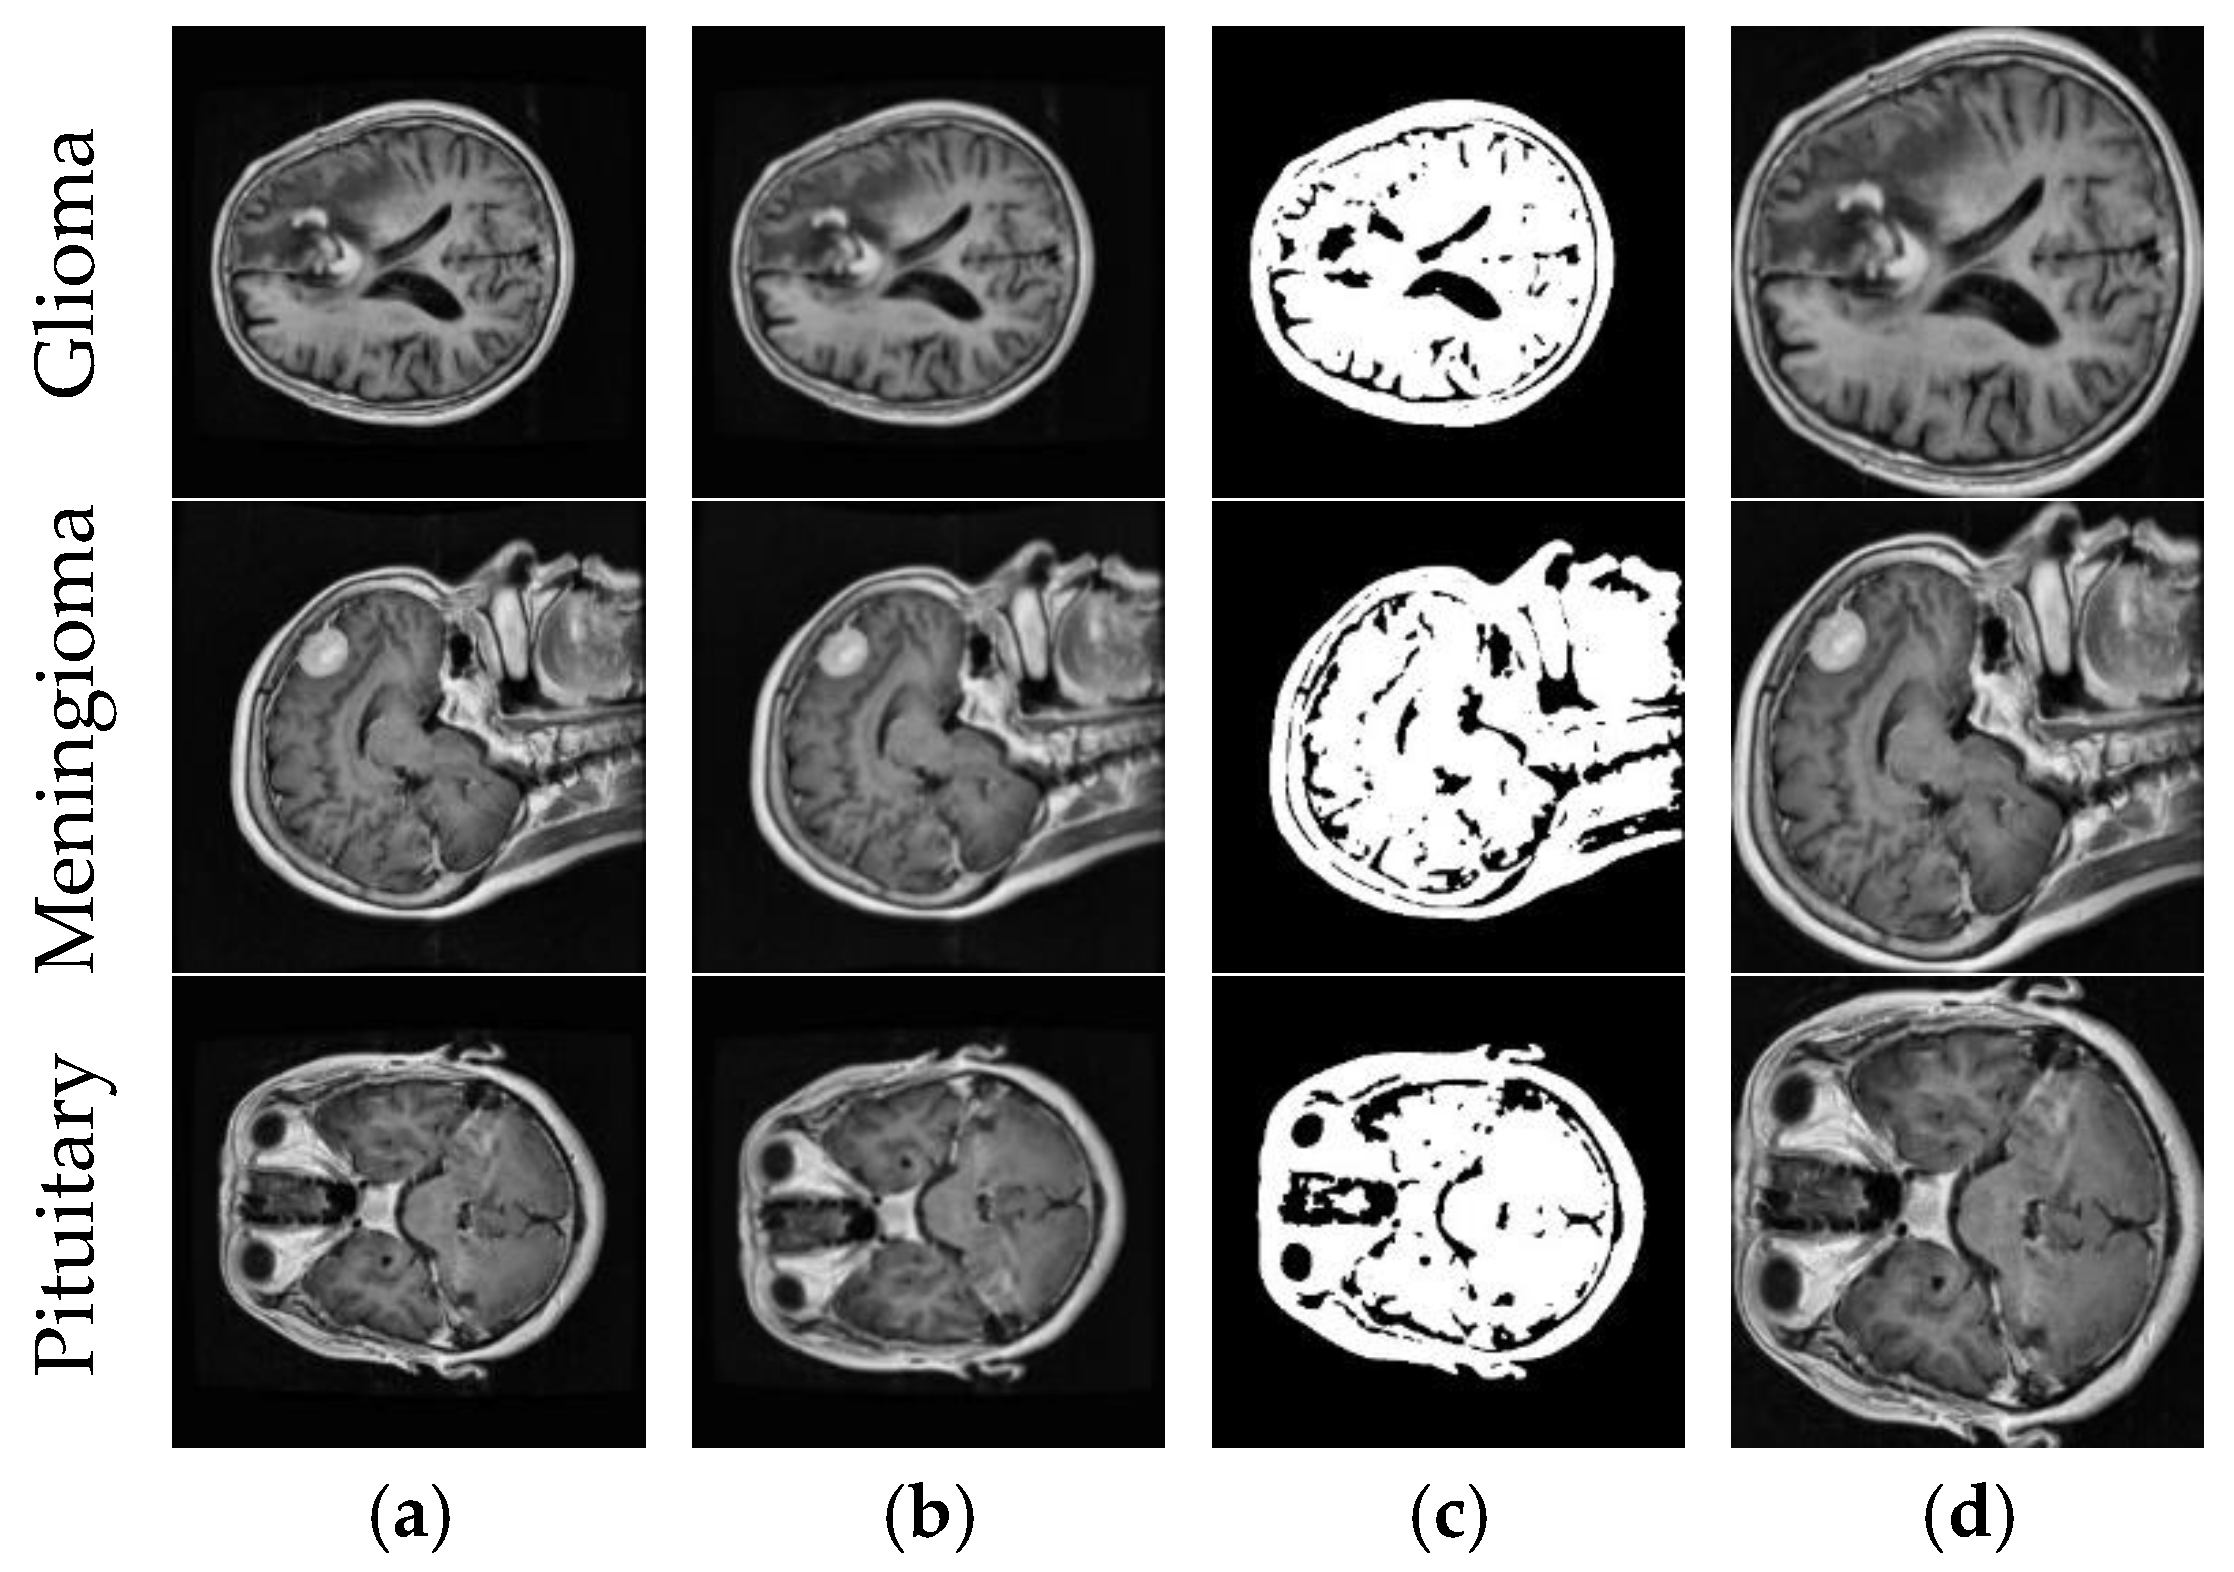

3.1. Dataset